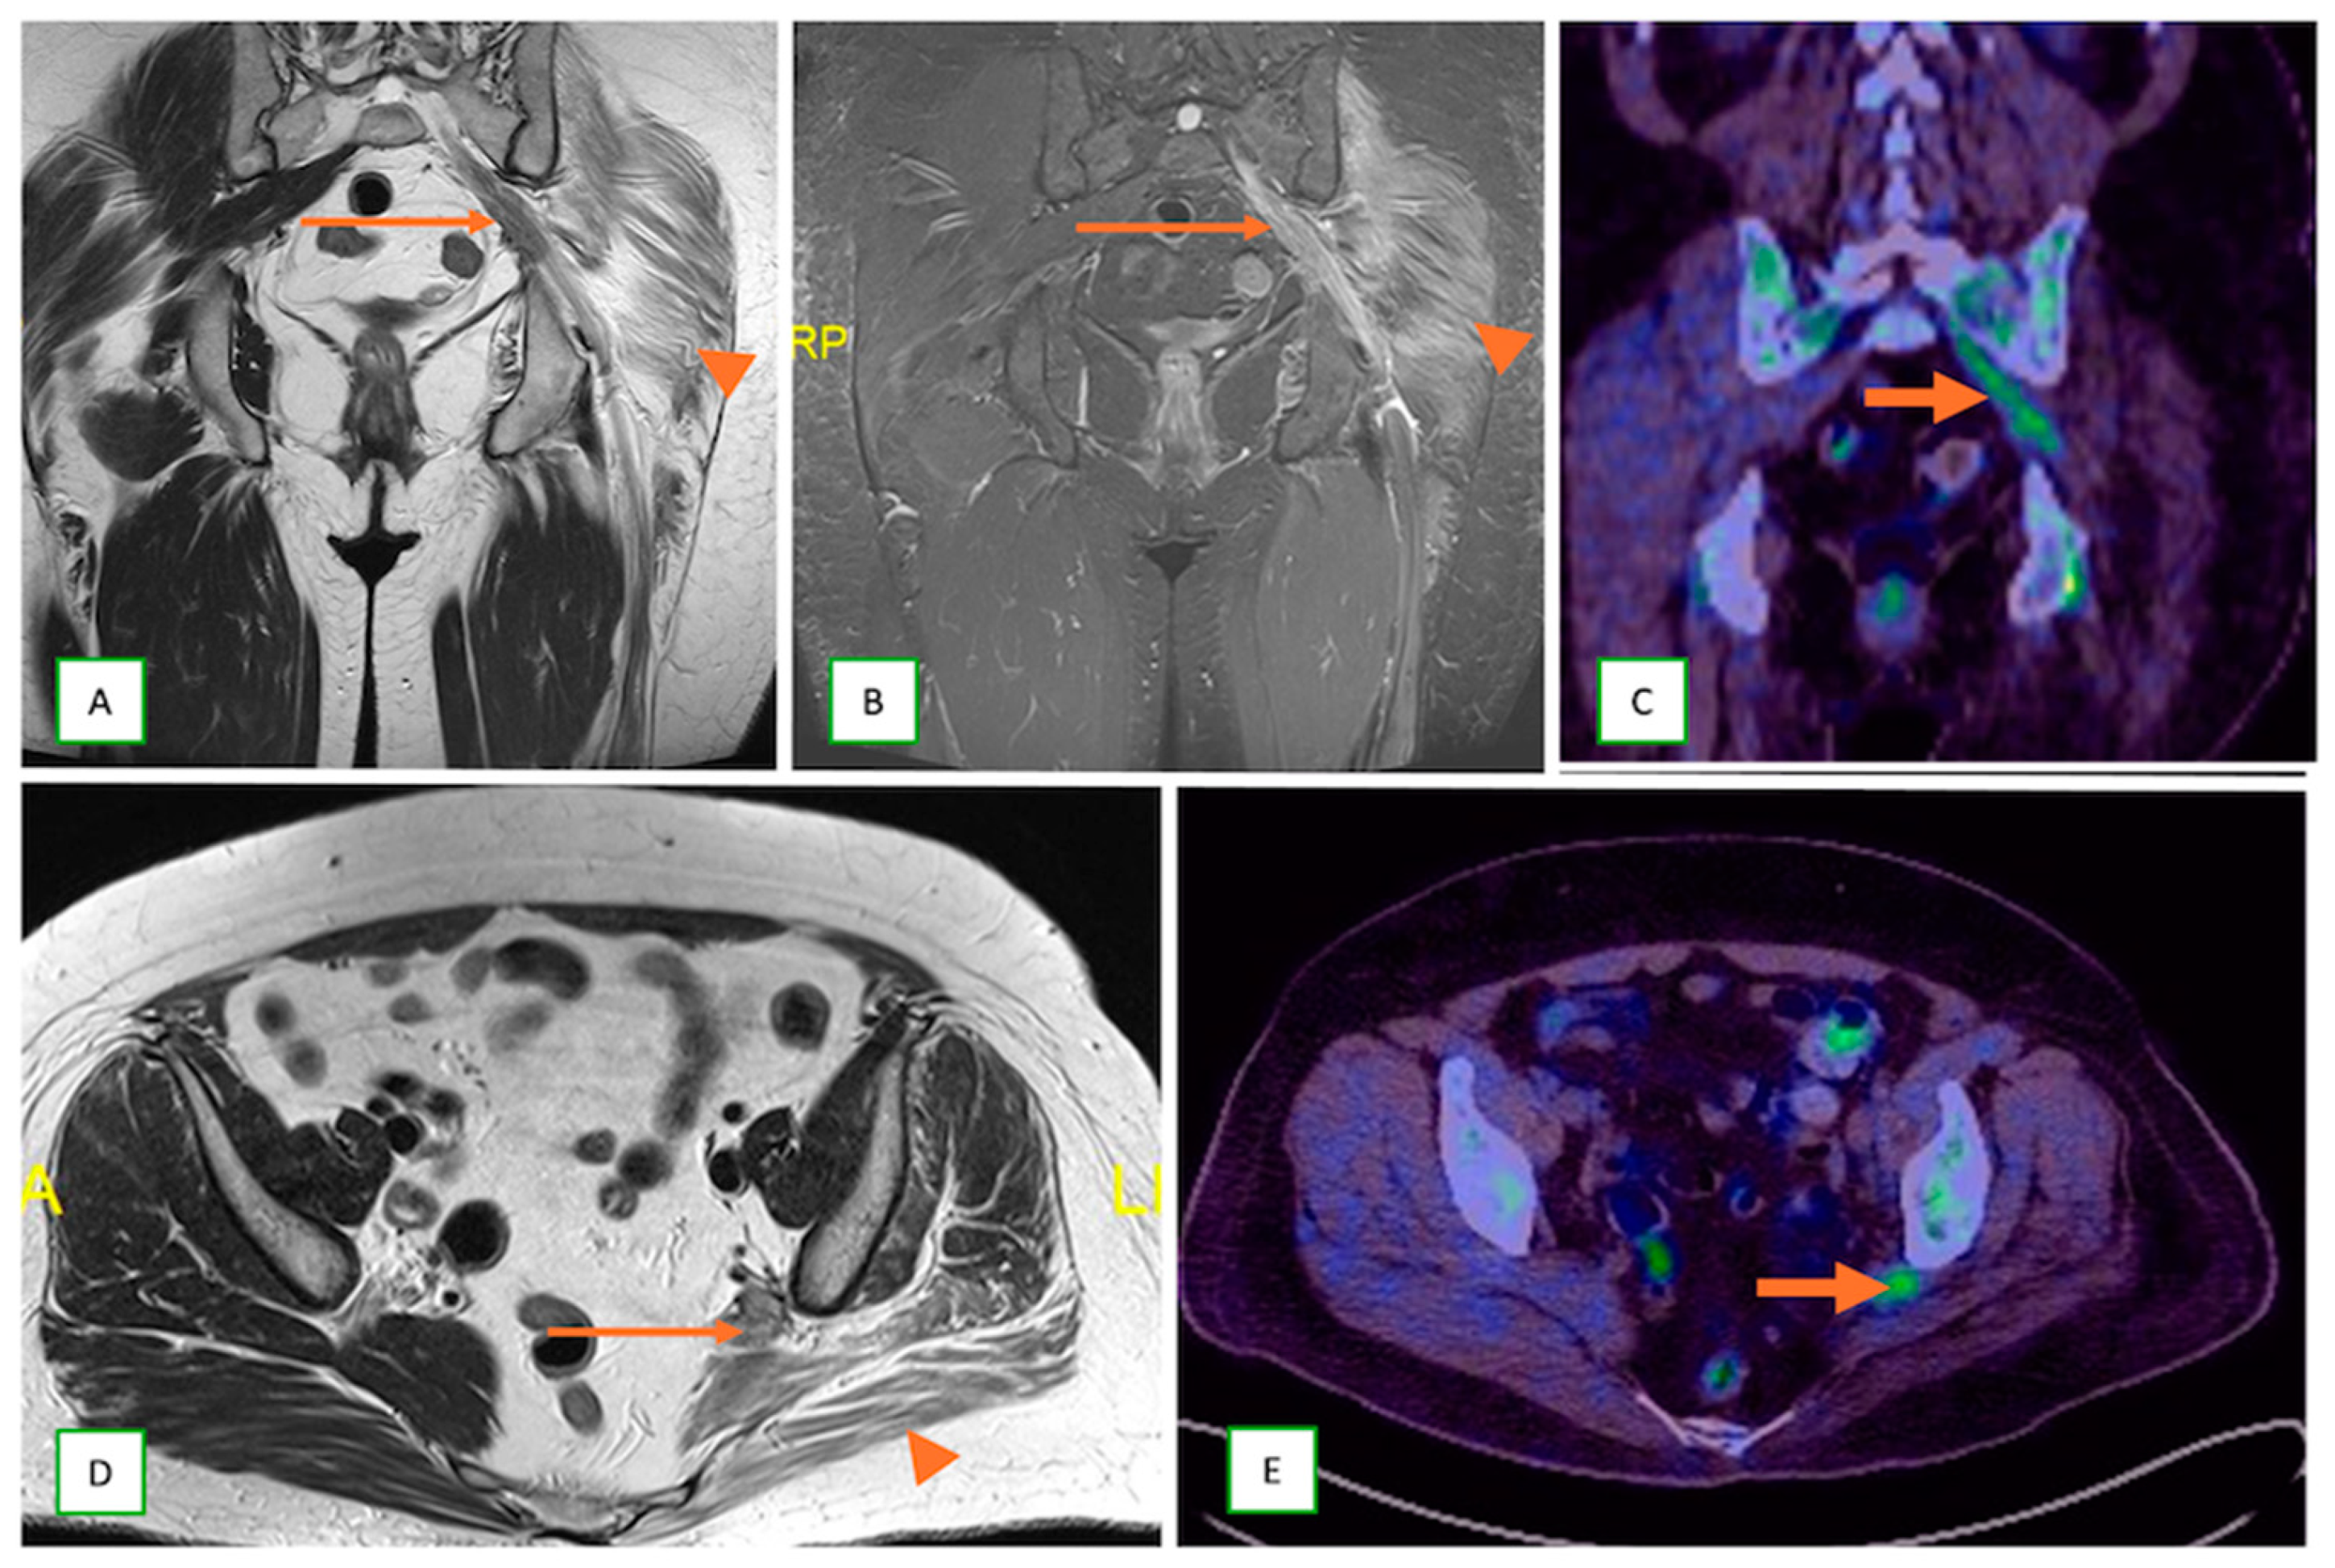

- Neurolymphomatosis describes intraneural spread of lymphoma and appears as diffuse enlargement of nerves, plexuses, spinal cord, and cauda equina. It shows more homogeneous enhancement than PNSTs and may be associated with lymphadenopathy or a known history of lymphoma [63] (Figure 20 and Figure 21).

- Metastatic lesions: These include perineural spread of the tumor or metastasis to peripheral nerves by an adjacent or distant primary tumor. They are commonly observed with head and neck cancers, such as squamous cell carcinoma. They typically appear as linear thickening and enhancement extending along the course of the affected nerve on MRI with end muscle edema and appear FDG-avid on PET-CT [66] (Figure 24 and Figure 25).

- Primary Sarcomas: Soft-tissue sarcomas are uncommon, accounting for just over 1% of adult malignancies. Synovial sarcoma, clear cell sarcoma, and epithelioid sarcomas are known to involve peripheral nerves. CT/MR reveals a large soft tissue mass with areas of necrosis or calcification and heterogeneous contrast enhancement. F-18 FDG uptake is useful for both tumor staging and treatment assessment (Figure 26, Figure 27 and Figure 28).